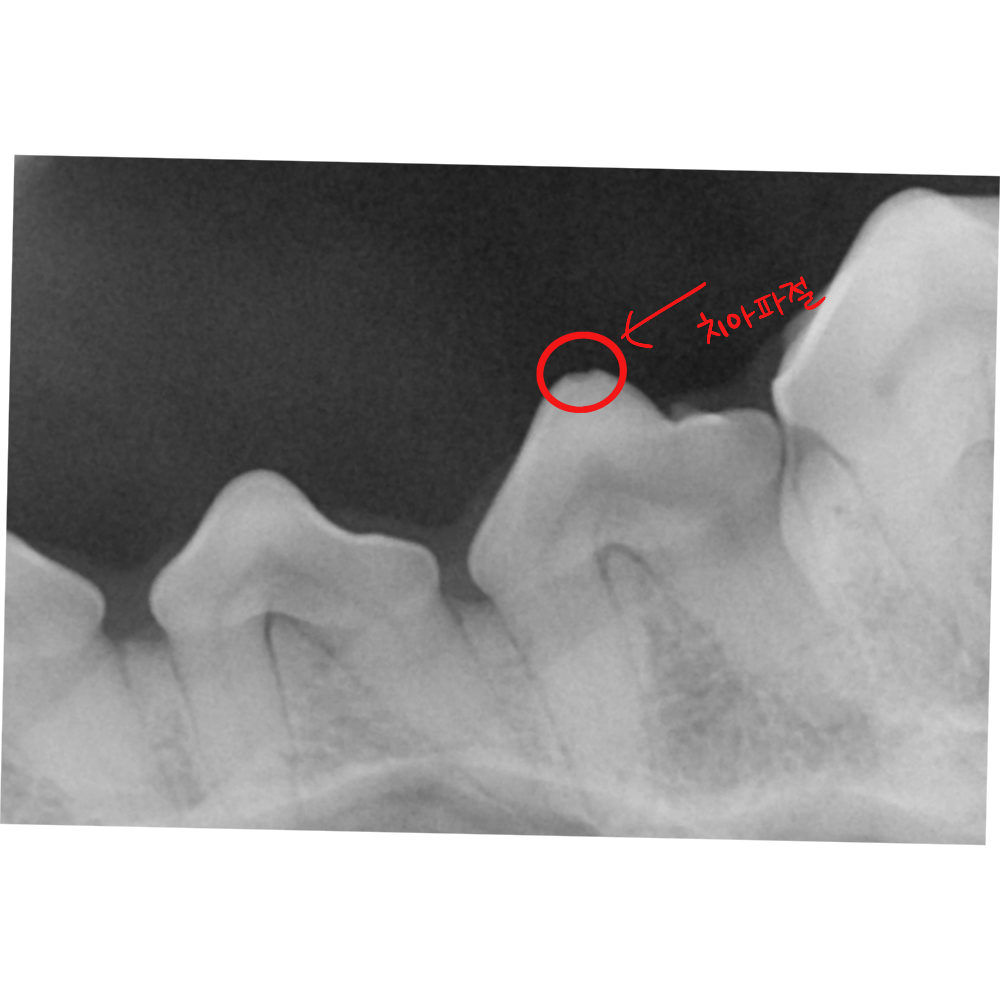

2. 구강 엑스레이를 통한 치조골 분석

발치 여부를 결정하는 가장 중요한 기준은 구강 엑스레이입니다. 치아 뿌리를 감싸고 있는 치조골의 높이가 얼마나 유지되고 있는지를 확인해야 합니다.

검사 결과, 해당 부위의 치조골 높이는 정상 범위 내에 있었고 뿌리 끝까지 진행된 골 소실은 관찰되지 않았습니다. 치아를 지탱하는 기반 구조가 유지되고 있다는 의미입니다.

잇몸 라인은 일부 내려가 있었지만 치아는 단단히 고정되어 있었고, 구강 엑스레이상 치조골의 높이도 유지되고 있었습니다. 치주낭 깊이 역시 적극적인 관리가 가능한 수준이었습니다. 치아 표면의 파절 또한 신경이 노출된 상태가 아닌, 법랑질 범위 내의 미세 파절로 확인되었습니다.